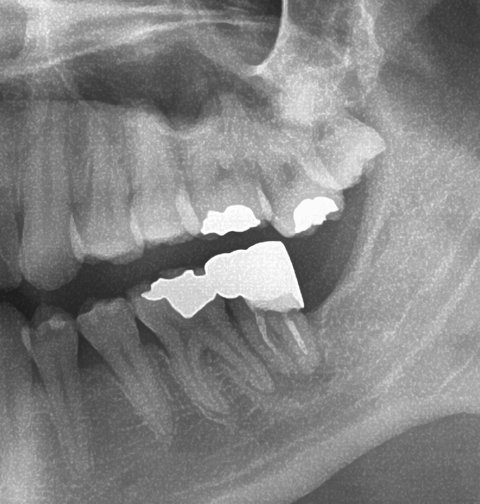

[배경]약 3년전 동네치과의원 A선생님께 진료를 받았습니다. 1차 진료시, 어금니 치아 뿌리가 많이 썩게되어, 신경치료 후 골드 크라운을 씌우라고 권유를 받았습니다. 당시에는 치료를 잘 받아서 2년동안은 아무런 이상없이 지냈는데, 치료후 2년1개월째가 되는 시점에 치료한 치아에서 통증이 발생되었습니다.

즉시 치과의원 A선생님께 2차 재진료를 해보니, 신경치료시 남은 잔뿌리가 전부 제거가 되지않아 내부에서 염증을 일으켰다고 진단하였습니다. 의사선생님도 어느정도의 의료과실을 인정하시어 1. 재신경치료 혹은 2. 임플란트를 하자고 제안했고, 이에 발생하는 비용은  6(A선생님):4(본인)로 나누자고 하셨습니다. 저역시 이에 동의하여 둘중 고민하다가 재신경치료를 하기로 결정하였습니다.

재신경치료를 받기전, 아시는분을 통해서 CT 촬영을 받을수있었는데, CT 판독에는 염증이 상당히 많이 퍼져, 신경과 뼈에 구멍이 났으며 여기로 계속 고름이 차오르는 상태니, 발치후 임플란트를 하라고 권유받았습니다.

아래는 X-ray 사진입니다. 파노라마에 조금 혐오가 있으신분들을 위해 미리 알려드립니다.